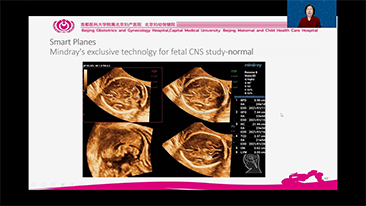

Didukung oleh platform ZST+ yang canggih, solusi cerdas yang lengkap dari Nuewa dirancang secara khusus untuk mendukung kesehatan kaum wanita yang lebih baik selama masa prakehamilan, kehamilan, dan pemulihan pascapersalinan, untuk menghasilkan diagnosis yang komprehensif dan efisien guna memenuhi tantangan klinis yang semakin meningkat.